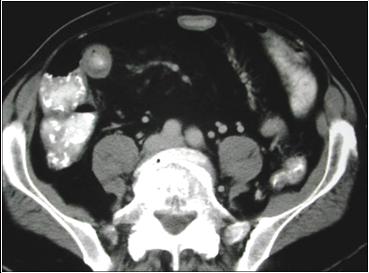

Double Halo Sign

2 alternating rings of density